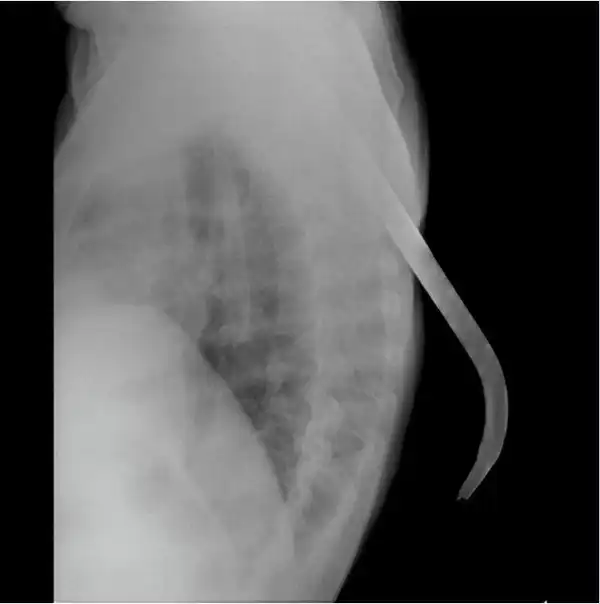

Мужчина упал на лом не повредив жизненно важных органов, говорят после операции выписан в удовлетворительном состоянии домой.